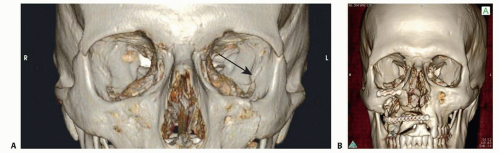

Post-traumatic, secondary enophthalmos occurs when the fracture pattern expands the volume of the bony orbit and is either uncorrected (FIG 2A) or reduced in the wrong position (FIG 2B):

As a result, the globe occupies a smaller percentage of the total space and assumes a more posterior position.

The most common cause of secondary enophthalmos during the primary operation is inadequate posterior dissection for fear of injuring the optic nerve or globe,2 followed by inadequate reduction of medial wall fractures (FIG 3).5